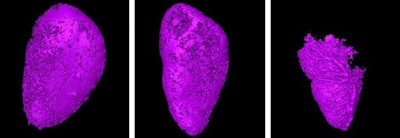

From left to right, micro-CT scans show decreasing visibility of contrast (violet) in the lymph node as tumors grow within. Images courtesy of Tohoku University.Approximately 28 days after the first injection, the researchers identified a noticeable reduction in contrast visibility within the lymph nodes, which they believe indicated the presence of cancer cells traveling through the lymph nodes to reach other regions of the body. This method could allow for the early detection of tumors before they fully metastasize, according to the group.